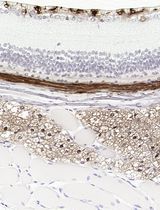

Figure 2. FJB-positive neurons in the mouse cerebral cortex following ischemic stroke

Fluoro-Jade is a fluorescent derivative used for histological staining of degenerating neurons. This technique is simple and sensitive enough to label distal dendrites, axons, axon terminals as well as neuronal bodies. Fluoro-Jade has excitation and emission peak of 480 and 525 nanometer respectively. It can be visualized using a fluorescein/FITC filter. Some reports have demonstrated that Fluoro-Jade can also be useful to detect glial cell death (Anderson et al., 2013; Damjanac et al., 2007).